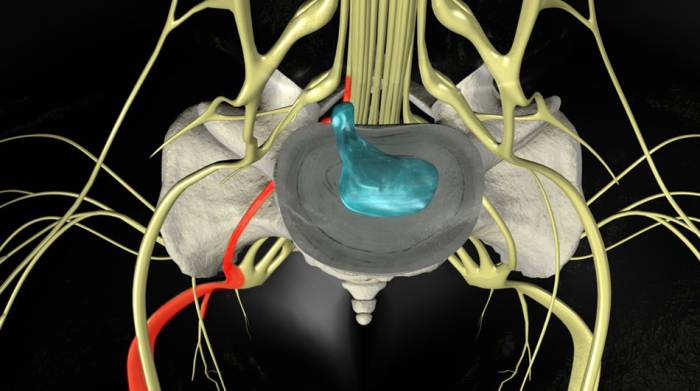

Дорзальная грыжа – это смещение (выпячивание) диска в просвет межпозвонкового канала. Смещение происходит из-за нарушений снабжения клеток позвоночника витаминами, минералами, аминокислотами, а также на фоне остеохондроза. Выпячивание межпозвонковых грыж происходит в наиболее ослабленном месте, что, к сожалению, невозможно предупредить.

Дорсальная грыжа межпозвонковых дисков отличается разным направлением в отношении спинного мозга, и в зависимости от этого заболевание делится на несколько видов:

- диффузная – разрушения происходят по всему диску;

- медиальная – основное ее направление – это центр;

- парамедиальная – смещается на половину канала;

- фораминальная – выходит в форамиальный канал, который образуется дужками позвонков, размещенных смежно;

- медиально-парамедиальная дорзальная грыжа – направляется от центра канала под углом в одну из сторон.

Наиболее опасной среди вышеперечисленных патологий межпозвонковых дисков является фораминальная. Связано это с тем, что фораминальный канал очень узкий и даже при смещении размером до 5 мм, уже может сдавливаться нерв. Очень часто заболевание локализуется на уровне l4 – l5 и l5 – s1 позвонков, реже — на l3 – l4.

Медиальная грыжа опасна тем, что может произойти сжатие спинно-мозгового канала. Если изначально она может иметь небольшие размеры и приносить незначительные болезненные ощущения, то в случае разрыва происходит большое выпячивание.

При большом размере медиальная грыжа сильно сдавливает спинной мозг в том месте, где она образовалась и вызывает парапарезы, а также всевозможные тазовые отклонения.